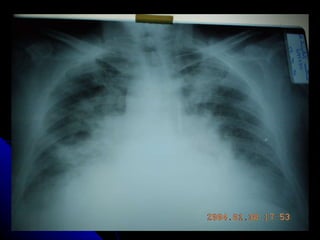

RADIOLOGIA Los infiltrados pueden ser muy pequeños y difíciles de apreciar especialmente en radiografías portátiles. La pausa inspiratoria es prácticamente imposible cuando el paciente se encuentra en ventilación mecánica haciéndolas menos específicas para el diagnóstico. La Tomografía Axial del tórax puede diagnosticar hasta en un 26% más, infiltrados pulmonares a más de definirlos más exactamente que la placa simple del tórax

RADIOLOGIA Los infiltradospueden ser muy pequeños y difíciles de apreciar especialmente en radiografías portátiles. La pausa inspiratoria es prácticamente imposible cuando el paciente se encuentra en ventilación mecánica haciéndolas menos específicas para el diagnóstico. La Tomografía Axial del tórax puede diagnosticar hasta en un 26% más, infiltrados pulmonares a más de definirlos más exactamente que la placa simple del tórax